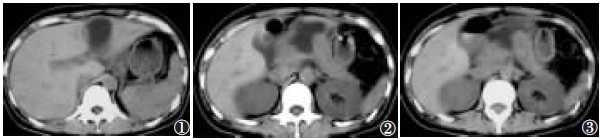

实验室检查:WBC16.81×109/L,RBC4.46×109/L,HGB134g/L。CT检查:胰腺肿大,边界模糊;胰腺体部前缘断裂,呈楔状裂隙,后部尚连接,远断端指向右前方(图1,2);其前方可见包裹状肿块,内含中等量液体,并向上延伸至肝裂(图3);CT诊断为胰腺部分断裂合并胰腺假性囊肿形成。

图1肝裂内可见圆形低密度影;图2胰腺体部前缘断裂,可见楔状裂隙,后部尚连接,远断端指向右前方;图3可见胰腺增粗,边界模糊,胰腺前方可见包裹性肿块,内含中等量液体,并向上延伸至肝裂